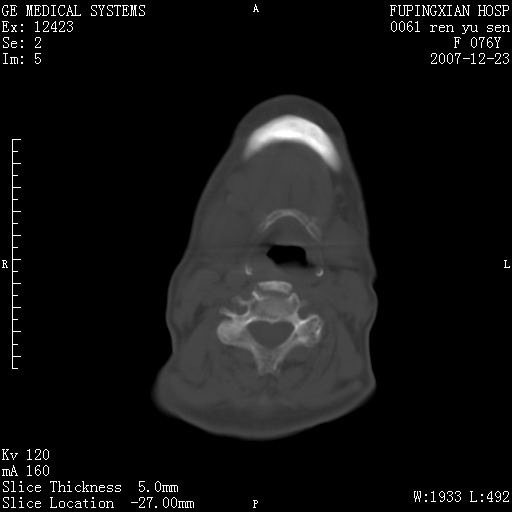

男性 76岁 下颌右侧磨牙区肿物数月, 约2.0*1.5cm大小波及颊舌侧,伴颌下淋巴结肿大。余(-)

右颈部颌下腺前可见一类圆形软组织密度影,密度不均,内见小片坏死区.颌下颈前可见两枚肿大淋巴结影.考虑淋巴结感染可能性大,建议增强扫描..

右侧第四磨牙缺失,局部牙槽骨质破坏,边界欠清晰,同侧颌下及竟不见多发肿大淋巴结显示。考虑肿瘤病变可能性大,感染待排